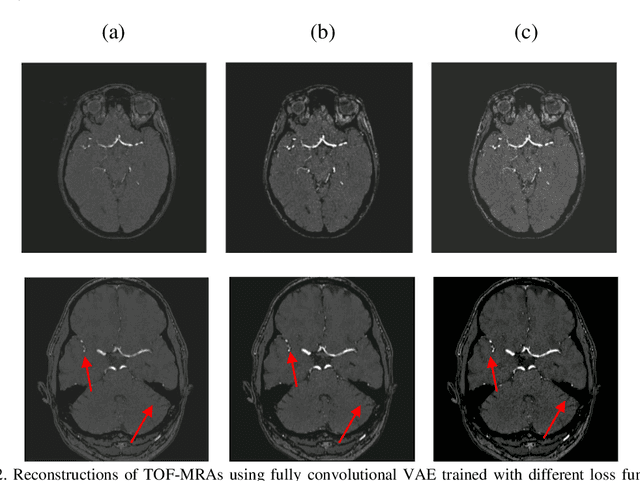

Abstract:Time-of-Flight Magnetic Resonance Angiographs (TOF-MRAs) enable visualization and analysis of cerebral arteries. This analysis may indicate normal variation of the configuration of the cerebrovascular system or vessel abnormalities, such as aneurysms. A model would be useful to represent normal cerebrovascular structure and variabilities in a healthy population and to differentiate from abnormalities. Current anomaly detection using autoencoding convolutional neural networks usually use a voxelwise mean-error for optimization. We propose optimizing a variational-autoencoder (VAE) with structural similarity loss (SSIM) for TOF-MRA reconstruction. A patch-trained 2D fully-convolutional VAE was optimized for TOF-MRA reconstruction by comparing vessel segmentations of original and reconstructed MRAs. The method was trained and tested on two datasets: the IXI dataset, and a subset from the ADAM challenge. Both trained networks were tested on a dataset including subjects with aneurysms. We compared VAE optimization with L2-loss and SSIM-loss. Performance was evaluated between original and reconstructed MRAs using mean square error, mean-SSIM, peak-signal-to-noise-ratio and dice similarity index (DSI) of segmented vessels. The L2-optimized VAE outperforms SSIM, with improved reconstruction metrics and DSIs for both datasets. Optimization using SSIM performed best for visual image quality, but with discrepancy in quantitative reconstruction and vascular segmentation. The larger, more diverse IXI dataset had overall better performance. Reconstruction metrics, including SSIM, were lower for MRAs including aneurysms. A SSIM-optimized VAE improved the visual perceptive image quality of TOF-MRA reconstructions. A L2-optimized VAE performed best for TOF-MRA reconstruction, where the vascular segmentation is important. SSIM is a potential metric for anomaly detection of MRAs.